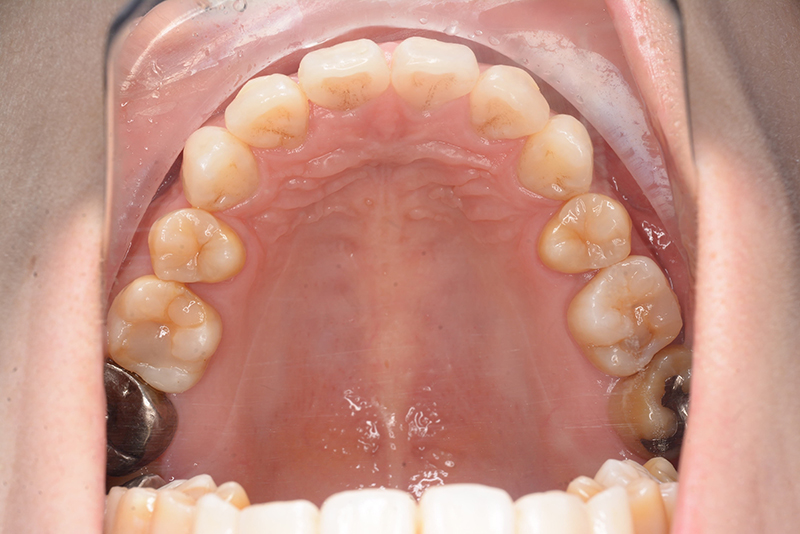

動的治療終了時

FP・IOP

批評・予后 治療後、緊密な咬合の確立と共に大幅な切歯の後退によって主訴である口元の突出感と口唇閉鎖不全の改善が得られた。